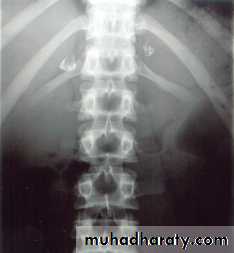

Tuberculosis cause adrenal calcification seen on plain abdominal X-ray